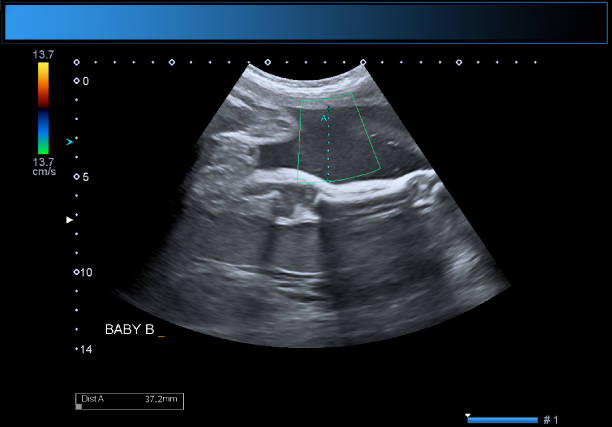

A tiffa scan in pregnancy—Targeted Imaging for Fetal Anomalies scan—is generally performed between the 18th and 22nd weeks. At this stage of pregnancy, the fetus has developed most of its important organs, and thus it would be the ideal time to assess physical structures and detect any abnormalities. At Dr. Aravind's IVF, the very best radiology team uses advanced ultrasound equipment so that even a clearer and more comprehensive image of the fetus is made available. This allows specialists to assess the baby's brain, heart, kidneys, spine, limbs, and other vital structures with utmost precision.

All steps of the tiffa scan procedure have been made safe, comfortable, and reassuring for every expected mother at Dr. Aravind's IVF. The whole scan usually lasts anywhere between 30 minutes to 45 minutes. During the scan, a trained sonologist slides a transducer over the patient's abdomen, taking high-resolution images of the fetus. Special preparation is not required from the mothers, but they might get a recommendation to keep their bladder moderately full for improved imaging. The Dr. Aravind's IVF team of experts details every step of the procedure, ensuring patients are calm and informed throughout the session.

In addition to performing routine imaging, the tiffa scan gives a detailed overview of overall well-being; it works great at detecting structural abnormalities, measuring fetal growth, examining placental position, and assessing amniotic fluid levels. At Dr. Aravind's IVF, should any developmental issues show up, doctors will use TIFFA results to work out an appropriate course of prenatal care. This method of early detection has assisted an innumerable amount of parents in taking steps toward a healthy result from a pregnancy. The scan will also highlight if it is a case of multiples and reverse twin growth if the pregnancy is of twins.